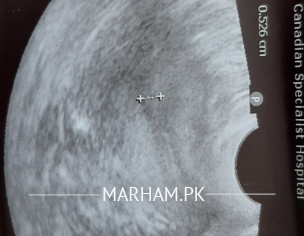

i have done Tvs on 7th day of cycle after a month of DnC. can you please explain my both ovaries are normal or polycystic? what is in utrus?? 2 picture are of ovaries one is of utrus. there is an arrow in my utrus what is it? please tell me my egg sizes on 7th day of cycle is normal or small.

your ovaries normal.no pcos and arrow shows thikening of lining of uterus